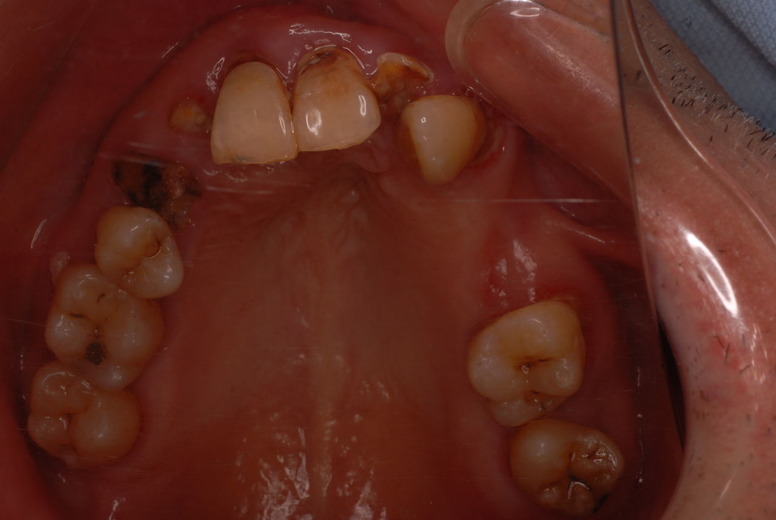

親知らずを取ることを嫌がる方が多いのですが、もし親知らずとその隣の14歳大臼歯の間に虫歯ができたり歯周病を罹患した場合、どれほど治療が大変で再発も起こりやすいか理解できない方がおおいのです。

写真左下の親知らずが痛くなり抜歯しました。その後歯茎を除去して虫歯を露出させる処置を二回ほどしています。

隣の14歳大臼歯がひどい虫歯になり治療不可能になりつつある状態のレントゲン